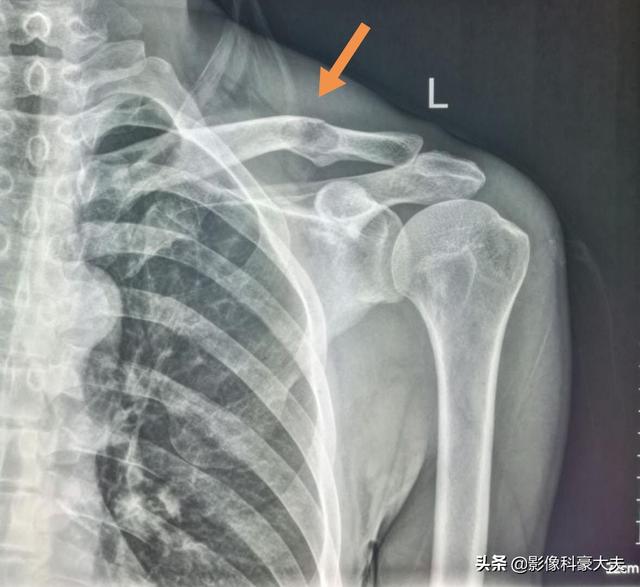

この症例は58歳のゲイ男性で、肩を軽く伸ばしただけで痛みが続くようになり、X線検査で低密度病巣が見つかった:

これは骨転移に基づく軽微な外力による病的骨折であった。穿刺が行われ、病理結果は低分化肺腺癌の骨転移であった。